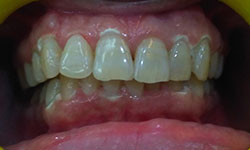

(15) Bleaching Teeth/Teeth Whitening

Before Treatment

After Treatment

Patient Reported to the clinic with a chief complaint of yellow teeth. Teeth Whitening was performed and 2 shade whiter results were achieved.